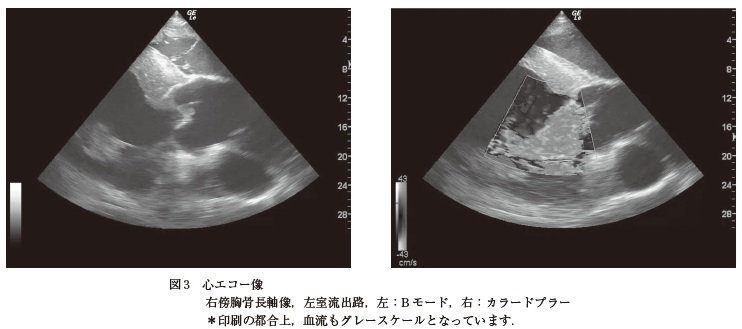

来院時検査所見:視診では右後肢の跛行(Grade3)があり,右飛節以下がやや腫脹していた.触診では腫脹部位の圧痛はあまりなく,飛節の熱感,屈曲痛,及び関節液の軽度増量がみられた.体温は38.1℃,安静時心拍数は52 回/ 分,安静時呼吸数は28 回/ 分であった.また,聴診では拡張期心雑音(Levine 分類3/6)が聴取された.身体検査ではその他に異常所見は認められなかった.臨床検査として,血液生化学検査(表),血清蛋白電気泳動検査(図1),飛節のX 線検査(図2),心エコー検査(図3,B モード及びカラードプラー)を行った.

微熱,頻脈,頻呼吸,拡張期心雑音(Levine 分類3/6)の聴取,白血球数の著しい増加,TPの高値,A/G 比の低下,グロブリン分画の増加,SAA の軽度高値,心エコー検査B モードでは大動脈弁の疣贅形成,さらにカラードプラーでは大動脈弁左心室方向への逆流がみられたことにより,大動脈閉鎖不全を伴う感染性心内膜炎に罹患していると考えられる.また飛節X 線像では踵骨載距突起部線状透亮像を認めるが,外力による骨折の可能性は否定できないものの,その形状がシャープではなく,そもそも当該部位は骨折の好発部位ではないことから骨折と診断しない.仮に骨折であれば,受傷時にGrade4以上の重度跛行を示すことが一般的であるが,本症例は重度跛行を示すことがなかった.したがって,本症例における右後肢の跛行及び関連した所見は,外傷や骨折によるものというより,感染性心内膜炎により引き起こされた転移性感染,免疫複合体沈着または塞栓に起因した関節炎の可能性が高いと考えられる.

次に,来院前に何らかの感染症の存在を疑っていたが,来院時の血液検査では,表及び図1 に示すように重度感染症を疑う結果であった.前述のとおり,跛行肢の局所身体検査では重度感染症を疑う兆候が乏しかったため,改めて全身の身体検査を行ったところ,拡張期心雑音,頻脈,頻呼吸が認められ,感染性心内膜炎を疑う所見が得られた.このため,心エコー検査(図2)を行った.心エコーB モードでは大動脈弁の弁尖が肥大し歪な形状となっており,疣贅が形成されていた.さらに,同部位におけるカラードプラーでは大動脈弁を左心室に逆流するジェット血流がみられ,そのジェット血流は心室自由壁に達していた.これらの所見から,感染性心内膜炎と診断した.